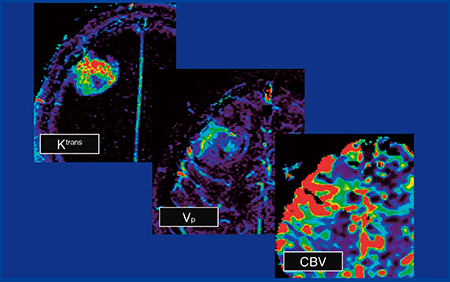

症例4(図4)の腫瘍は均一で境界明瞭であり,extraのmeningiomaのように見えたが,permeabilityを行うと,Ktransは高めであるもののmeningiomaほど高値ではなく,glioblastomaと判断した。

当院の検討では,meningiomaとHGGを比べると,KtransやCBVはmeningiomaの方が高い値を示す傾向となった。通常のMR画像にpermeabilityやperfusionの画像を組み合わせることは鑑別に有用であると考えられる。

図4 症例4:glioblastoma